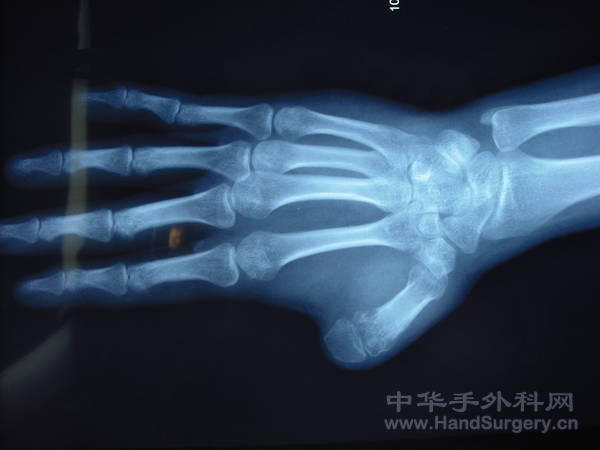

也发一例另类拇指再造

IMG_1841.JPG IMG_1831.JPG IMG_1832.JPG IMG_1833.JPG IMG_1834.JPG IMG_1835.JPG IMG_1836.JPG IMG_1837.JPG IMG_1840.JPG IMG_1842.JPG IMG_1844.JPG